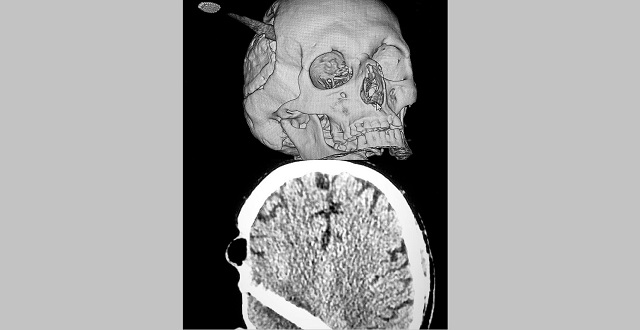

В Казани врачи Республиканской клинической больницы (РКБ) спасли жизнь мужчины, который поступил к ним с воткнутой в голову зубной щеткой. О необычном случае рассказала пресс-служба медучреждения в Instagram.

Мужчина с инородным предметом в голове поступил в РКБ поздно ночью, пациент находился в сознании. Проведение экстренной компьютерной томографии показало, что жизненно важные участки мозга задеты не были. Мужчину срочно забрали в операционную. О том, как щетка оказалась в голове, умалчивается.

Хирурги ювелирно извлекли щетку из головы. Мужчина мог умереть в любую секунду от внезапно открывшегося кровотечения, но пациенту несказанно повезло, он буквально «родился в рубашке». После проведения пластики кожных покровов, которая длилась на протяжении четырех часов, операция завершилась успешно.